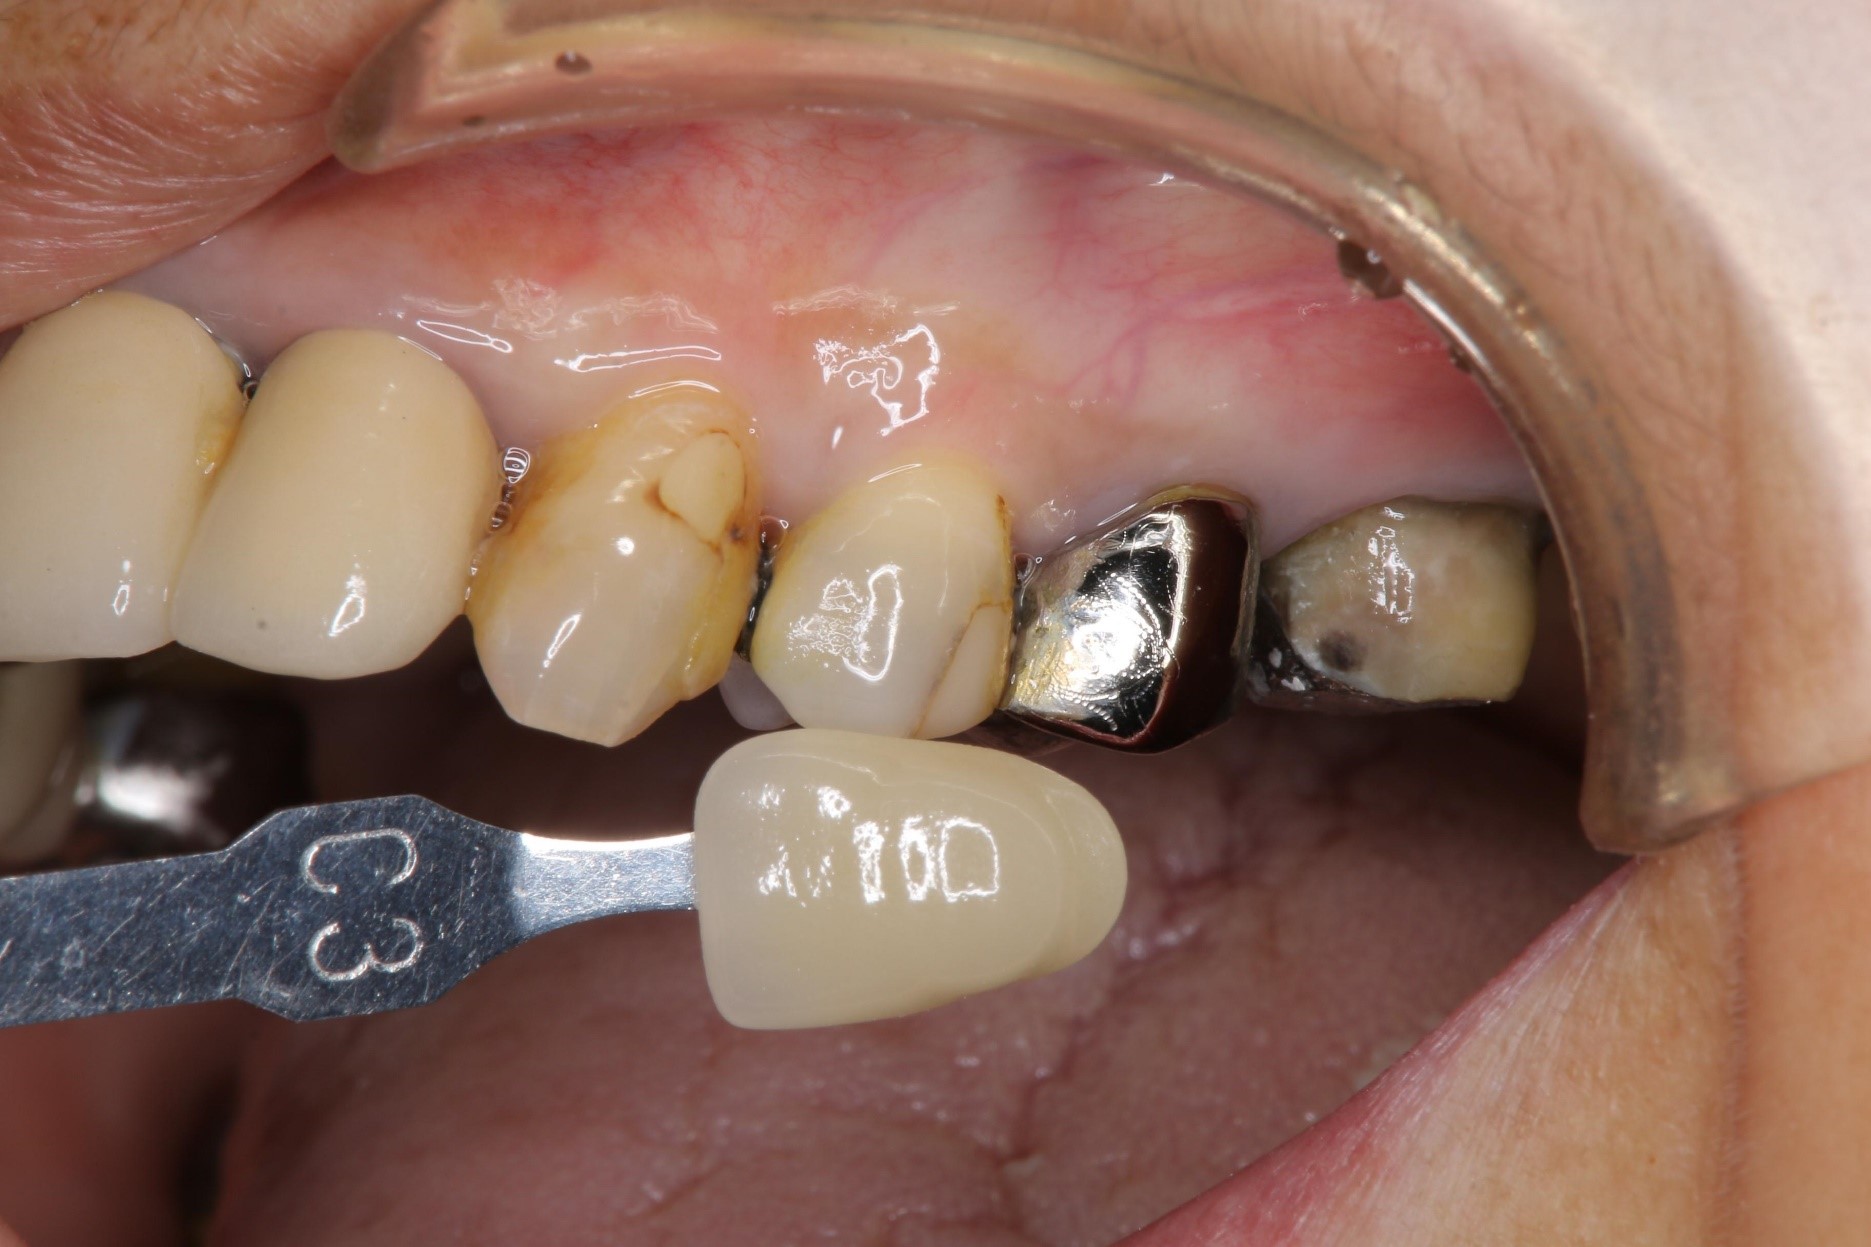

膺復前評估牙齦、牙齒狀態

照相比色